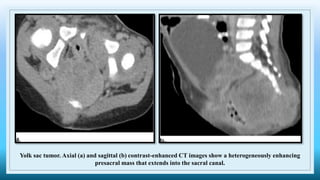

Yolk sac tumor. Axial (a) and sagittal (b) contrast-enhanced CT images show a heterogeneously enhancing

presacral mass that extends into the sacral canal.

• Yolk sac tumors have a more aggressive imaging appearance than teratomas and are

characterized by more heterogeneous soft tissues and areas of hemorrhage and necrosis

• CT, areas of low attenuation with no enhancement are seen, and at T1-weightd MR imaging,

areas of hyperintensity are seen, a finding related to hemorrhage.

• Yolk sac tumors demonstrate heterogeneous contrast enhancement and often invade adjacent

organs.